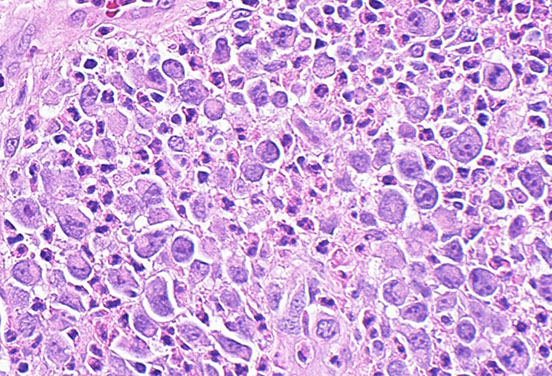

LyP type A

LyP - Scattered large cells with scattered smaller cells and neutrophils (mixed inflammatory background) wiht eos

LyP

LyP type C with diffuse sheets of CD30+ cells